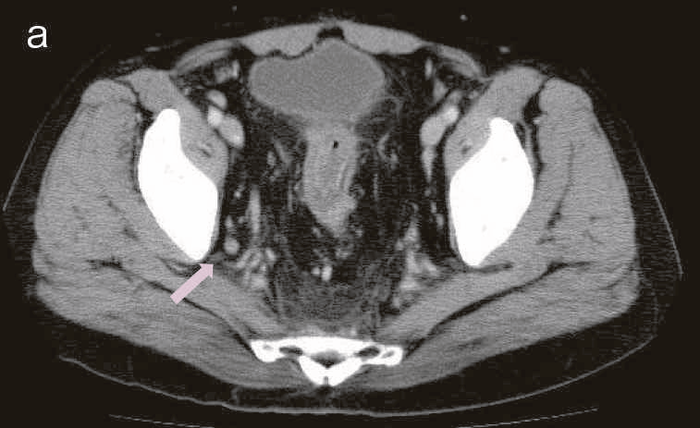

精査で施行したCT,MRIで痔瘻癌が疑われた。

図43 腹部骨盤CT

CTではMRIと同様に広範囲のhigh density areaがあり,癌と炎症が波及した領域の区別がつかず右側方領域にリンパ節腫大を認めた。